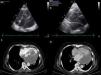

The patient was referred to the oncology clinic and maintained in follow-up. Two months later she was readmitted with dyspnea. The tumor had grown, with a left ventricular mass (59 mm×35 mm) protruding into the outflow tract causing obstruction (peak systolic gradient of 54 mmHg), plus a pericardial mass (Figure 4). The patient died suddenly one month later.

(a and b) Transthoracic echocardiogram (modified 4-chamber view) showing a left intraventricular mass measuring 59 mm×35 mm protruding into the left ventricular outflow tract, extending to the pericardium and infiltrating the left ventricular wall; (c and d) computed tomography angiography showing an intracardiac mass occupying the entire left atrium and part of the left ventricle, extending to the pericardium and compressing the inferior vena cava.